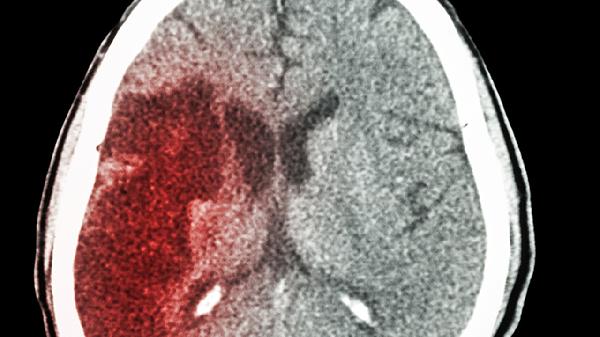

外傷腦出血開(kāi)顱手術(shù)恢復(fù)后能活多久

外傷性腦出血開(kāi)顱術(shù)后患者的生存期通常可達(dá)5年以上,具體時(shí)間與出血量、術(shù)后護(hù)理、康復(fù)訓(xùn)練、基礎(chǔ)疾病控制及并發(fā)癥預(yù)防密切相關(guān)。

腦出血量直接影響腦組織損傷程度。30毫升以下的出血經(jīng)及時(shí)手術(shù)清除后,神經(jīng)功能代償空間較大;超過(guò)50毫升的出血可能遺留永久性功能障礙,需通過(guò)高壓氧治療和神經(jīng)修復(fù)藥物促進(jìn)恢復(fù)。